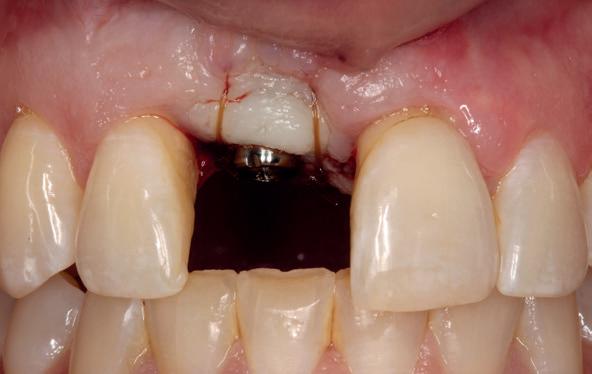

Implantologische behandelingen in het esthetische front vragen meer dan technische vaardigheid alleen. Ze vragen om overzicht, timing, vertrouwen en een team dat als vanzelf samenwerkt onder druk. Juist bij complexe casussen, waarin angst, infectie en hoge esthetische verwachtingen samenkomen, wordt zichtbaar hoe bepalend de rol van de tandartsassistent is.

Deze casus beschrijft een uitgebreide immediate implantaatbehandeling bij een patiënt die door meerdere collega’s werd geweigerd. Niet omdat de mogelijkheden ontbraken, maar omdat de complexiteit vroeg om een perfect afgestemde samenwerking. Het verhaal laat zien hoe de assistent in zo’n traject veel meer is dan een uitvoerende kracht of “mal”, maar een dynamische surgical guide die het proces mede stuurt, bewaakt en mogelijk maakt.De patiënt: wanneer alles samenkomt

Na het klinische onderzoek volgde het röntgenologisch traject. De CBCT liet precies zien wat we al vreesden: een front waarin het bot onregelmatig was, duidelijke radiolucenties rond de pijlers en een infectiegebied dat zich onder vrijwel de gehele brug had verspreid. Tegelijkertijd was er ook potentie. Net voldoende botstructuur om immediate implantaatplaatsing te overwegen, mits alles perfect gepland zou worden.